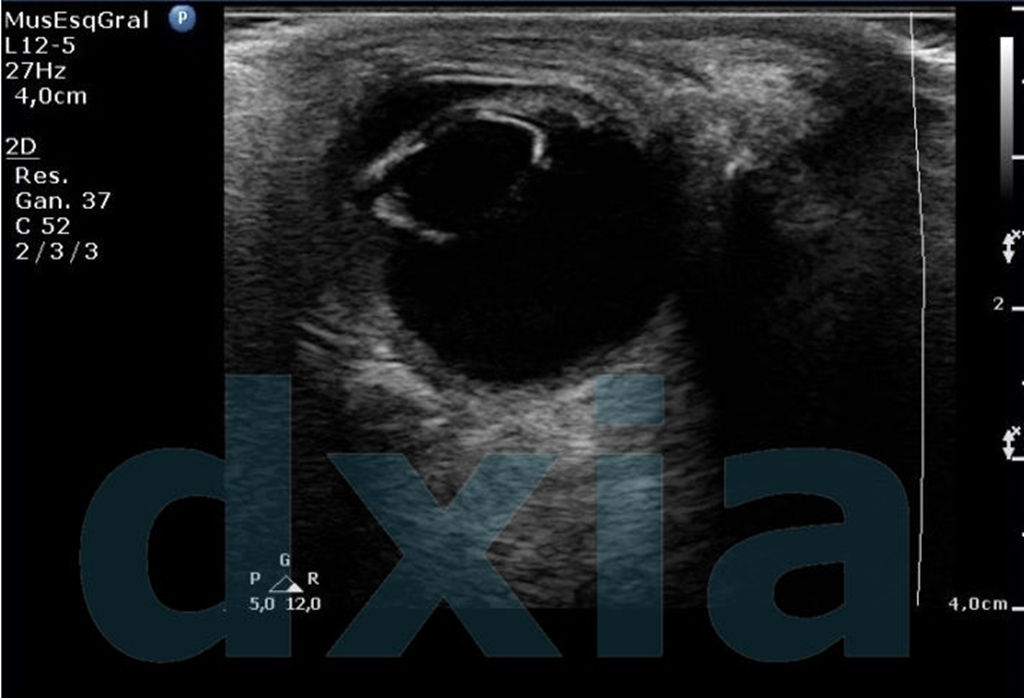

El estudio de ecografía ocular (modo 2D) se realiza con sonda de alta frecuencia. Está indicado para la obtención de varios diferenciales como desprendimiento de cristalino o de retina, masas intraoculares o retrobulbares, hemorragias, detección de CE…

Mediante el uso de la ecografía ocular en modo B podemos detectar cuerpos extraños, hemorragias intraoculares, cataratas, alteraciones en el cristalino, neoplasias, desprendimiento de retina, vítreo primario persistente congénito…